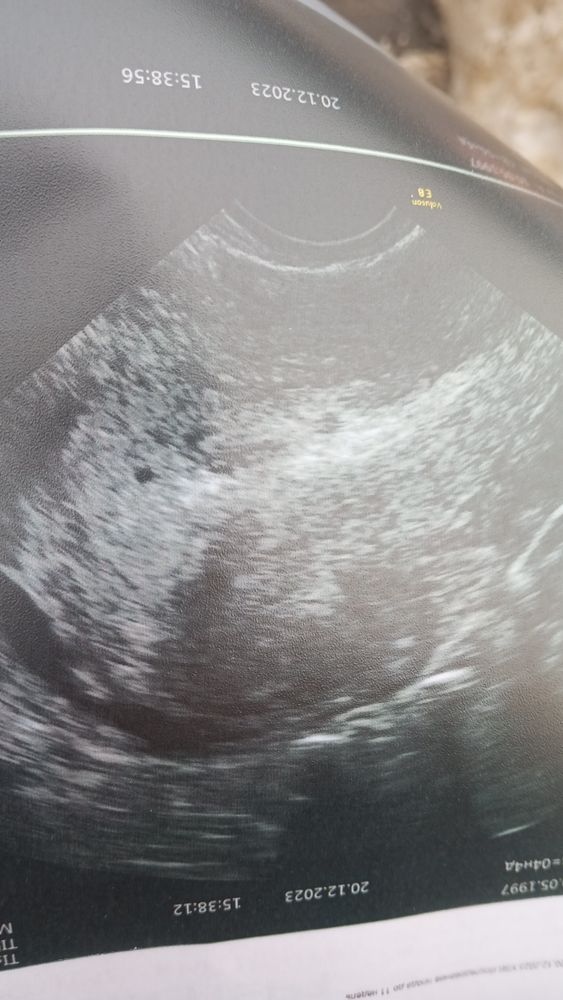

Срок 4.5. Хгч сегодня 381.Пошла сегодня на УЗИ. Ничего увидеть там не надеялась. Меня беспокоил левый яичник. В итоге и правда, кистозное ЖТ и увеличенный левый яичник. В остальном все хорошо. И вот уже после осмотра труб, яичников я слышу в самом конце:"ах, вот ты где прятался!". Совсем кроха 2мм . я такая счастливая 😍